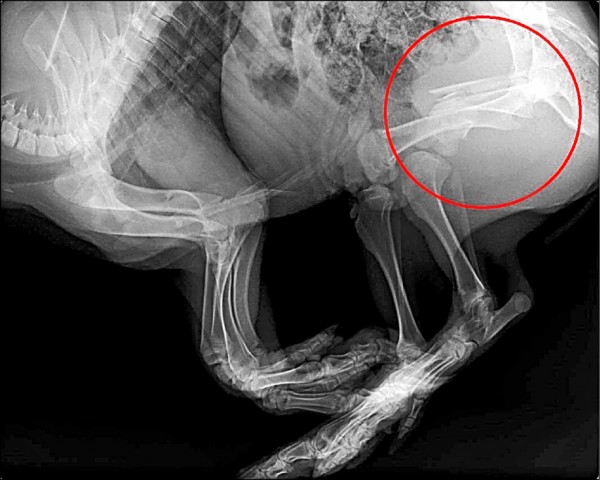

不過員警們覺得陳姓飼主當下渾身酒氣,不能完全採信他的說詞,而且山豬怎麼會連籠子一起從高處摔落,於是在現場進行蒐證後將山豬遺體送到中興大學附設獸醫學院解剖釐清確切死因。直到上週診斷結果出爐,山豬全身多處骨折,且有顱內出血的現象,判斷並非意外摔落,與陳姓飼主的說法相差甚遠。